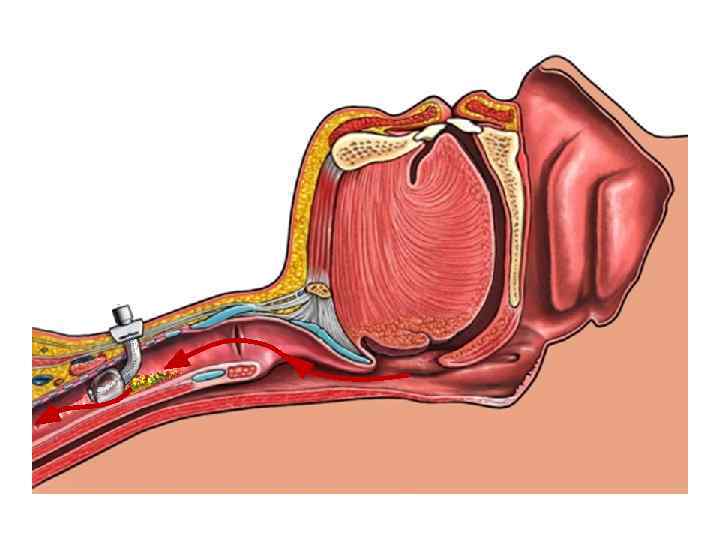

Интубированный больной надгортанник Интубационная трубка как распорка, позволяет стекать содержимому ротоглотки в трахею

Интубированный больной надгортанник Интубационная трубка как распорка, позволяет стекать содержимому ротоглотки в трахею

Интубация или трахеостомия надгортанник Интубационная трубка блокирует голосовые складки и надгортанник

Интубация или трахеостомия надгортанник Интубационная трубка блокирует голосовые складки и надгортанник